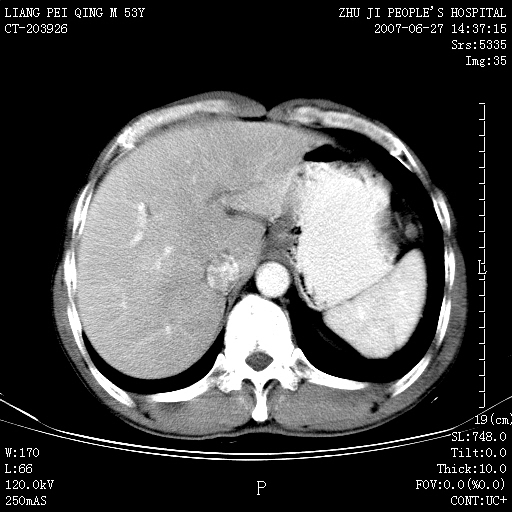

以下是引用余辉在2007-6-27 18:46:00的发言:[br]病灶多发,内可见大片状低密度区,病灶病灶等密度区轻度强化,动脉期后期病灶低密度区与高密度区对度增加,考虑1淋巴瘤2转移瘤3血管内皮细胞瘤(不知有否静脉期及延迟期扫描)

以下是引用zzzzhhhhaaaannnn在2007-6-27 20:44:00的发言:[br]脾脏 肋骨转移可能性大,下腔静脉内有癌栓

以下是引用狙击手在2007-6-28 10:35:00的发言:[br]1:定位:来源于脾脏。2:强化:强化,但不均匀。3:下腔静脉癌栓?下腔静脉充填不均匀与增强时间有关,延时即可明确。4:肋骨破坏?看起来并不确切。综上考虑几个最常见诊断:1;淋巴管瘤;2;血管内皮肉瘤(高度恶性,早期即可转移,常见肝,肺,骨)3;转移瘤(无特征性,只有肝或其它腹腔脏器有类似病变时,才可提示之)